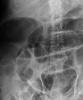

Sistema ureterocalicial doble